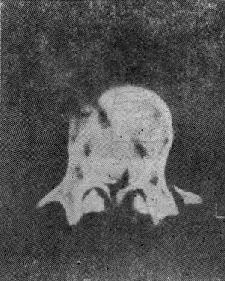

(三)爆裂型骨折 是由沿身体纵轴作用的暴力造成的骨折。椎间盘被压入椎体终板,进入松质骨内致伤。椎体由中央“爆炸”样裂开,将骨折片推向四方,有椎体后缘骨折,且有骨折片突入椎管内(图73-3)。椎弓根之间的距离裂开、增宽。常合并后方椎板的纵行骨折,前方椎体裂开越大,椎板骨折就越明显(图73-4)。有时仅有椎板内板骨折,要CT扫描才能发现。爆裂型骨折又可分成五种:①同时有上、下终板损伤,伴有椎体后缘骨折片突入椎管,压迫脊髓,产生神经系统症状;②椎体上半部骨折,椎体后方压缩,有骨折片旋转进入椎管内,此型最多见;③下方椎体终板损伤;④爆炸型合并有旋转骨折,除有爆裂型骨折特征外,还可见旋转棘突偏歪一侧;⑤爆炸型骨折合并侧方压缩骨折,骨折线斜行过椎体,椎弓根距离增宽,椎体两侧高度不一样,常伴有多发横突骨折,此型最不稳定。

爆裂型骨折

图73-3 爆裂型骨折

椎板纵行骨折

图73-4 椎板纵行骨折

爆炸型骨折的主要特点为:椎弓根间距增宽,椎体后部压缩,高度变小,及椎体横径增宽。几乎所有爆裂型骨折都具有神经系统症状。